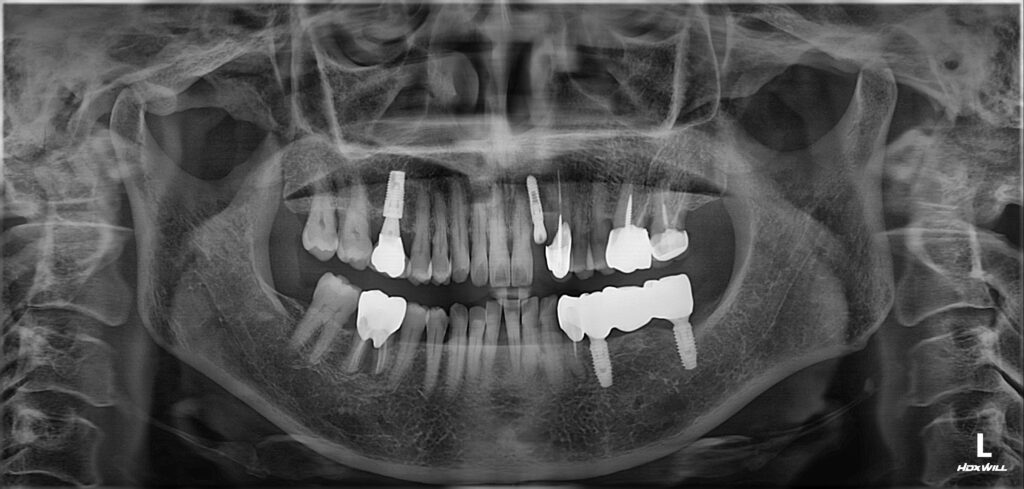

보험 임플란트 가능하셨고

콜라겐을 함유하고 있는 블럭형태의 골이식재를

사용하는 것이 움직임이 적기 때문에

더 예지성있는 형태를 만들수 있을 것으로 생각하여

진행하기 전 CT 촬영을 통해 정밀한 진단을 바탕으로

치료를 계획하였습니다.

뼈이식 후 임플란트 식립을 진행한 모습입니다.